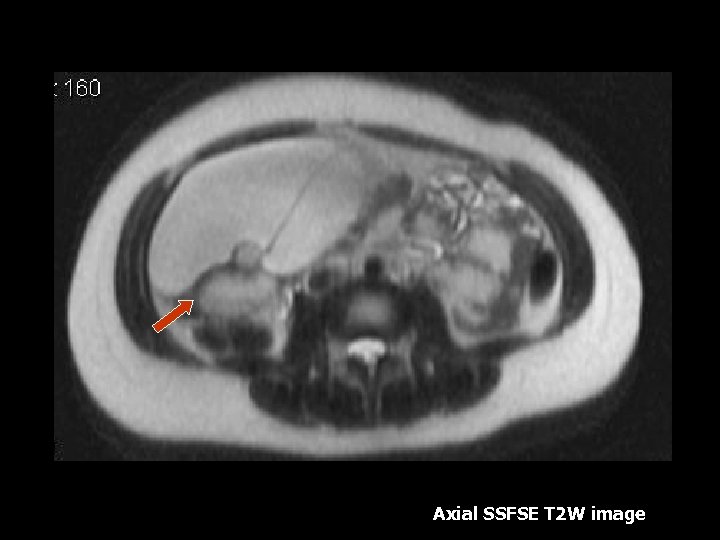

Axial SSFSE T 2 W image

Mature Cystic Teratoma • 25 -58% of all benign ovarian tumors, 70% if age <19 (6). • Dermoids contain mesodermal, ectodermal and endodermal elements (6). • Typically an epithelial lined cyst filled with sebaceous fluid, debris and hair (6). • Intralesional mural nodule(Rockitansky nodule) is identified in >90% which may contain fat, teeth(7%)or calcifications(18%) (6). • Common complication: Torsion which occurs in 16% of cases(6). • Rare complication: Rupture(1%), Infection(1%), Autohemolytic anemia(1%), Malignant transformation(12%) (6). • Malignant transformation should be suspected if size greater than 10 cm and postmenopausal age(6).

Mature Cystic Teratoma • Characteristic MR features: Fat within the teratoma can be diagnosed with T 1 weighted, T 1 with fat suppression(2, 4). • Other MRI findings: Fat-fluid levels, dermoid nipple or mural nodule, and intracystic fat balls(7). • Calcium and bone is present will demonstrate low intensity on all pulse sequences(7).